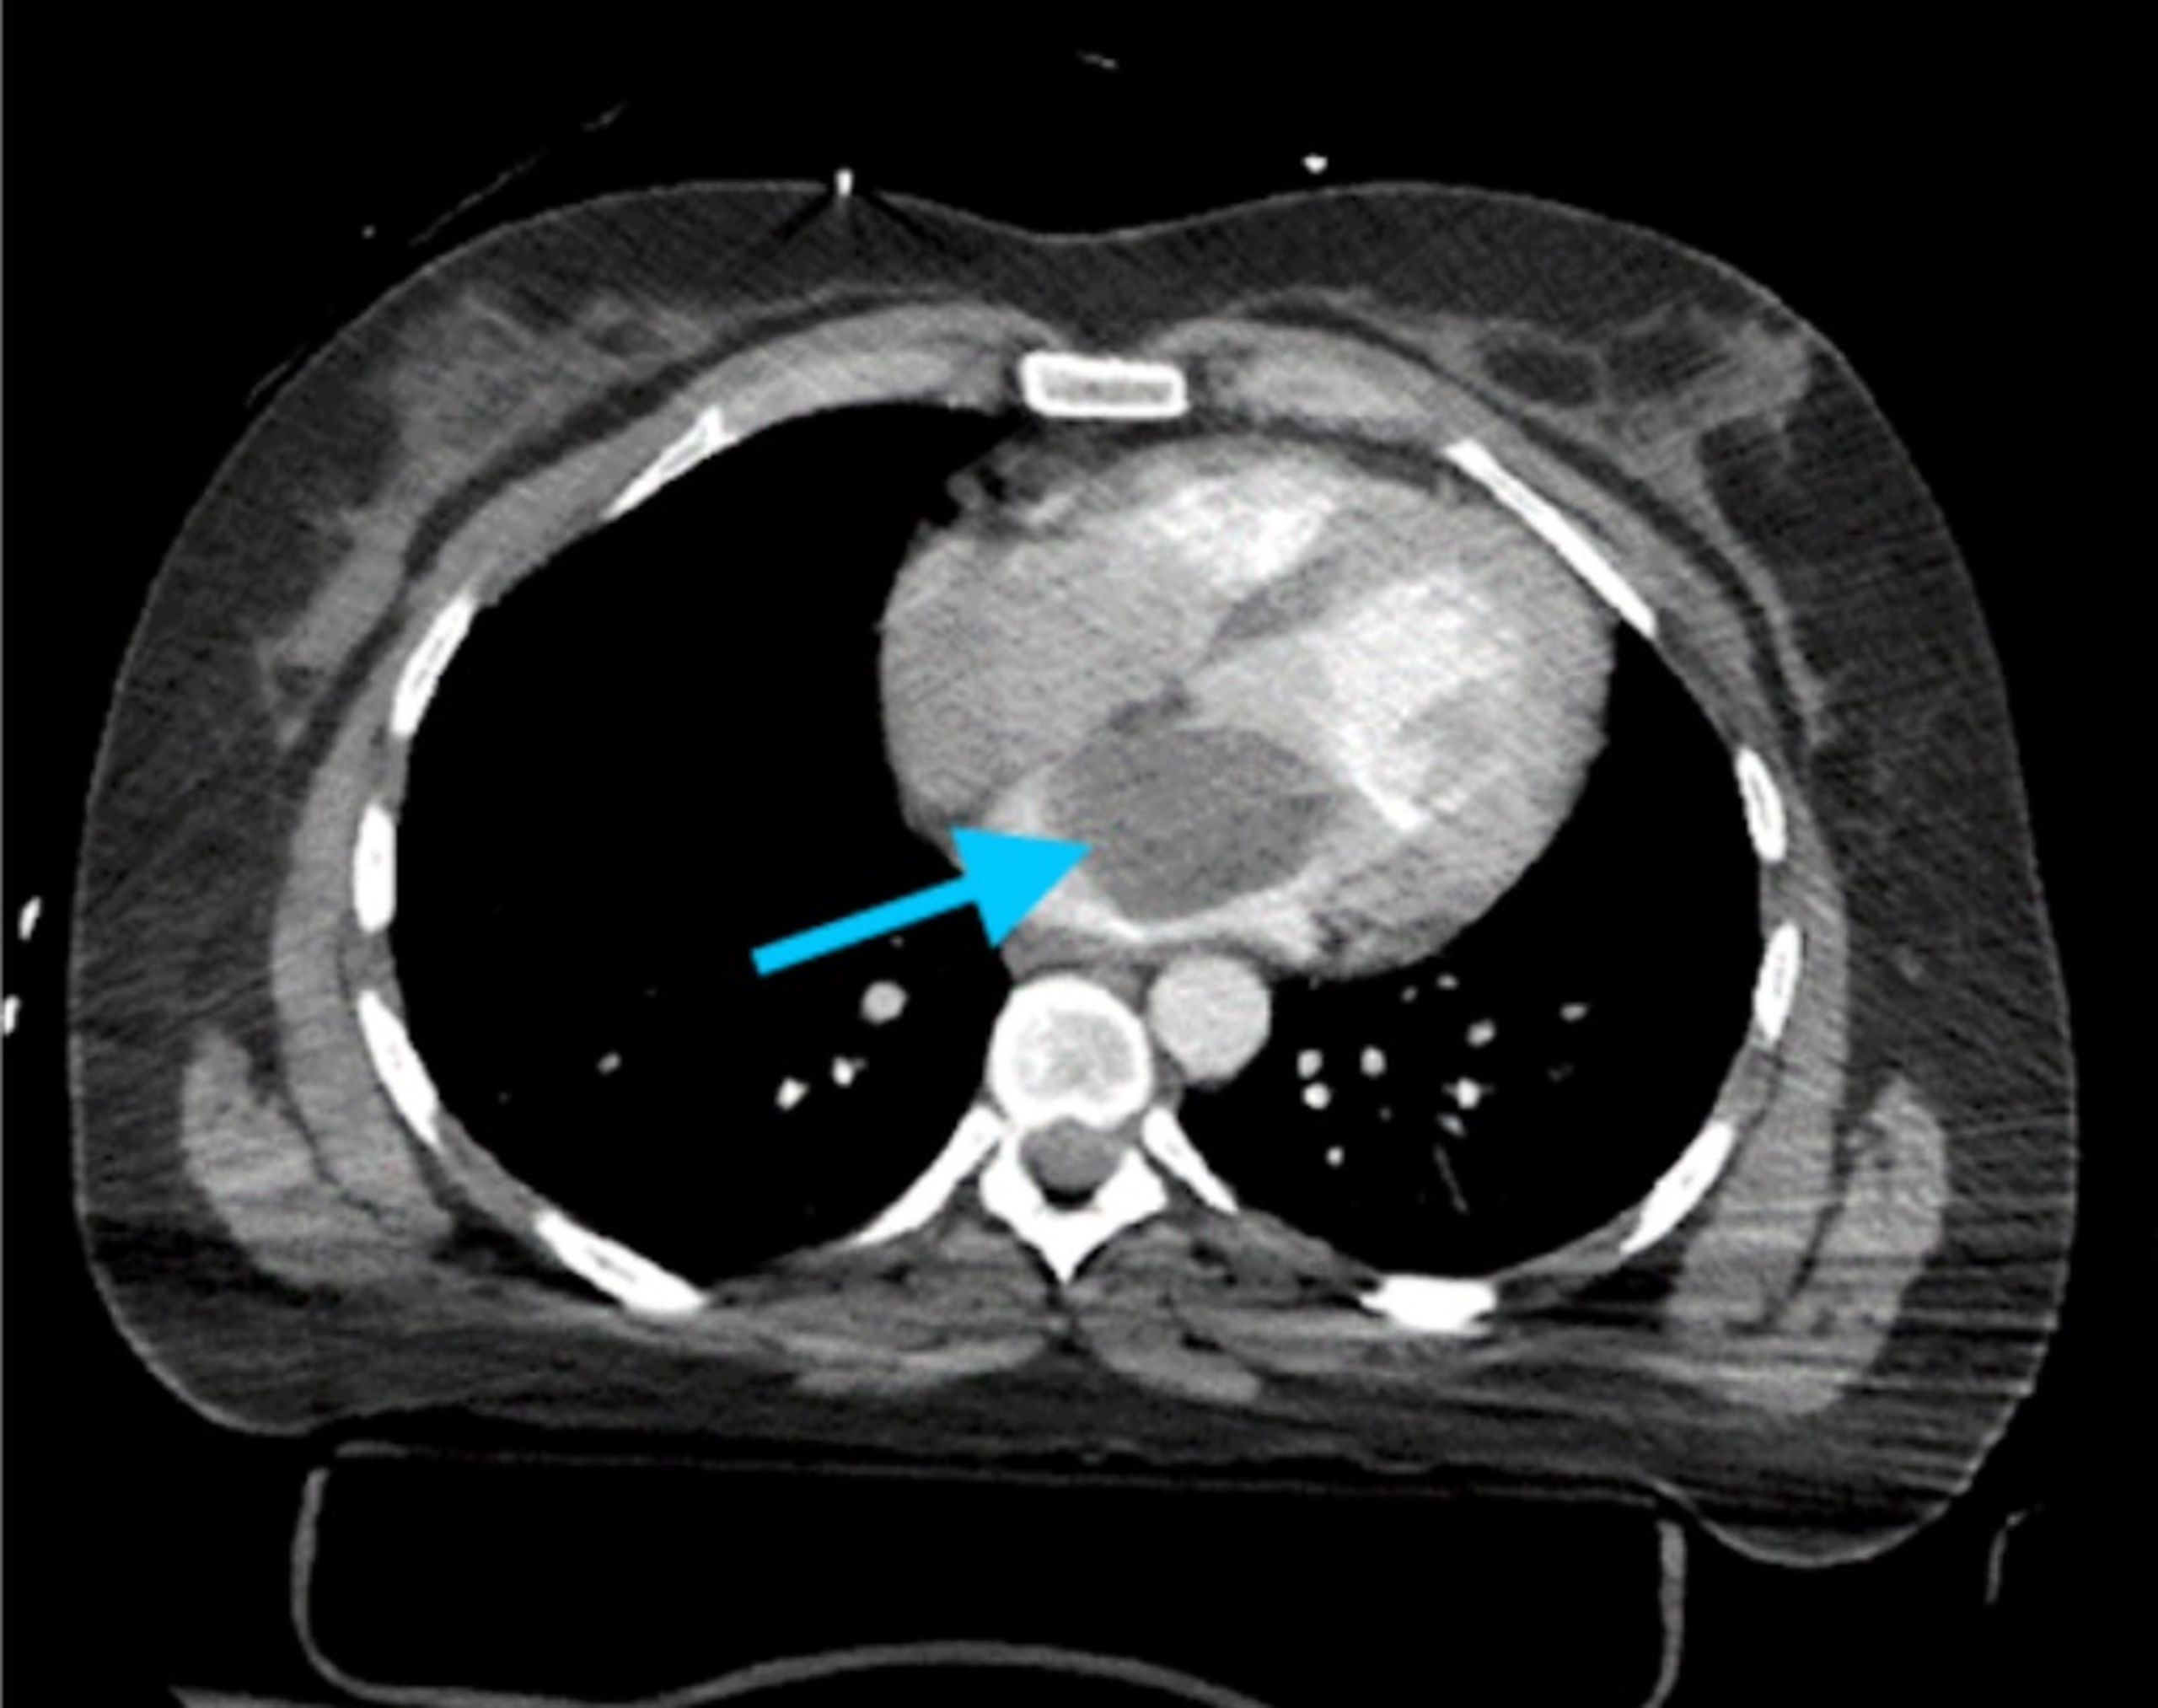

U trong tim là các khối u mọc bất cứ nơi nào của tim, như cơ tim, lớp nội tâm mạc (lớp màng bao bọc bên trong tim) hoặc lớp ngoại tâm mạc (lớp màng bao bọc bên ngoài tim).

Cũng như các cơ quan khác trong cơ thể, u trong tim có thể là u lành tính hoặc ác tính. U ác tính nguyên phát ở tim rất hiếm, đa số là lành tính (chiếm tỷ lệ trên 75%) và thường gặp nhất là u nhầy nhĩ trái.

Loại u phổ biến nhất, chiếm 50% trong các khối u nguyên phát ở tim. Tỷ lệ mắc bệnh ở phụ nữ cao gấp 2 - 4 lần nam giới. Khoảng 75% trường hợp u nhầy xuất hiện ở tâm nhĩ trái.

Đường kính của u nhầy đôi khi lên đến 15 cm. Khoảng 75% u nhầy có cuống và có thể sa xuống van hai lá và cản trở đổ đầy tâm thất trong thời kỳ tâm trương. 25% còn lại là u không cuống và chân rộng. U nhầy dính và nhầy; nhẵn, mủn và không đều hoặc chắc và có thùy. Các khối u mủn, không đều có nguy cơ gây thuyên tắc hệ thống.